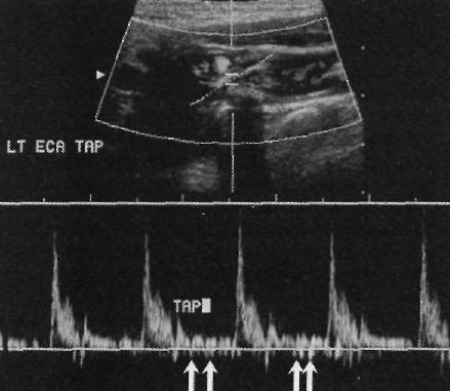

Постукивание по височной артерии позволяет дифференцировать наружную сонную артерию с внутренней. Процедура подразумевает постукивание пальцем по ипсилярной височной артерии во время проведения допплерографии наружной сонной артерии. При этом кривая записи кровотока наружной сонной артерии должна демонстрировать характерные волнообразные колебания, которые соответствуют постукиваниям по височной артерии, являющейся ветвью наружной сонной артерии (фото 2).

Фото 2. Височное постукивание. Стрелкой обозначены колебания, вызванные постукиванием по височной артерии во время проведения допплерографии

Отметим, что височное постукивание может демонстрировать ложноотрицательные результаты. Это может быть обусловлено недостаточно сильным постукиванием пальцем по артерии. Также бывают случаи, когда при нормальном состоянии артерии пульсация распространяется на общую и внутреннюю сонные артерии.